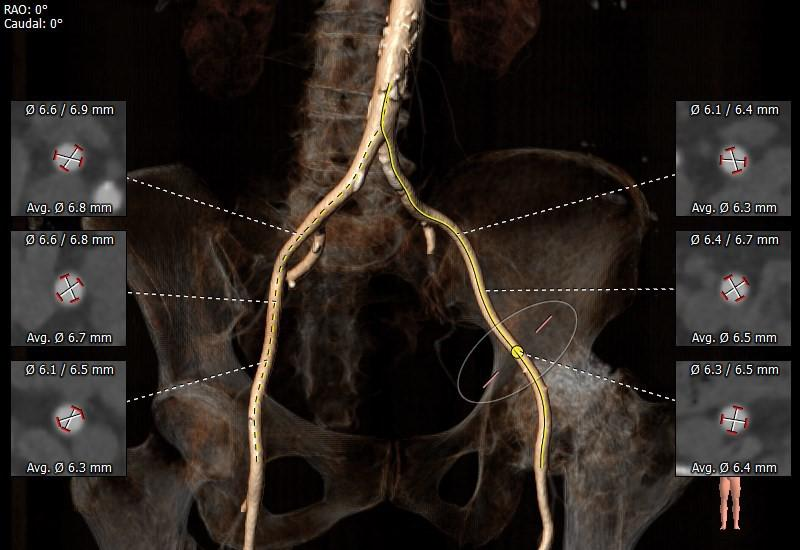

外周血管及主动脉弓解剖

OVERVIEW

入路血管散在钙化,双侧血管内径良好,整体入路血管条件良好